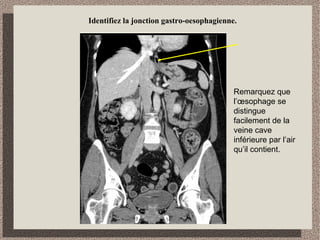

Identifiez la jonction gastro-oesophagienne.

Remarquez que

l’œsophage se

distingue

facilement de la

veine cave

inférieure par l’air

qu’il contient.